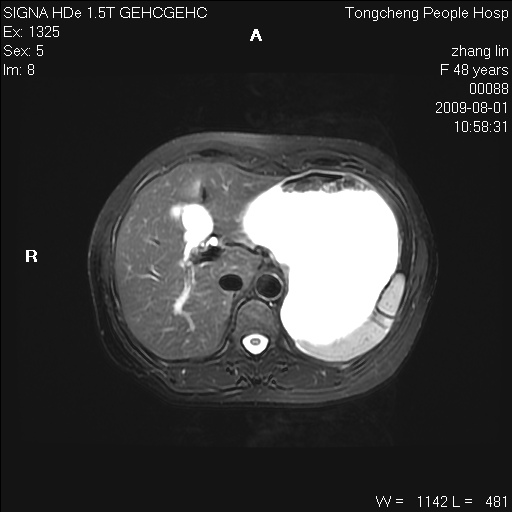

女,48岁。健康体检,彩超发现右肾占位性病变。平素健康。

临床诊断:右肾占位性病变,性质待定(囊肿?肿瘤?)。

上中腹部mr平扫+增强扫描,图像如下:

右肾上极见一类圆形病灶,t1wi呈等信号t2wi呈等高混杂信号,三期增强无强化,边界清---考虑囊肿出血。

同反相位均表现为等信号,病变无强化,考虑含蛋白的囊肿可能,弥散加权相或许有些帮助,

肝囊肿

慢性胆囊炎